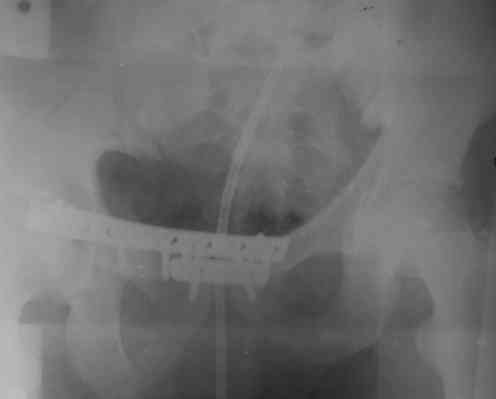

Уважаемые коллеги! На днях оперировал перелом таза месячной давности - разрыв симфиза, перелом обеих ветвей правой лонной кости, трансфораминальный перелом крестца слева. Представляю рентгенограммы с задержкой - технические причины.

Предоперационные рентген и КТ, в операционной - снимки после каждого фиксатора. Вертикальное смещение полностью устранить не удалось. В первую очередь за счет заднего полукольца. Хотя при компрессии на стержнях горизонтальное смещение было сантиметра 1,5. Т.е. крестец, на мой взгляд еще не сросся. От коллег хотел-бы услышать допустима-ли такая остаточная деформация?